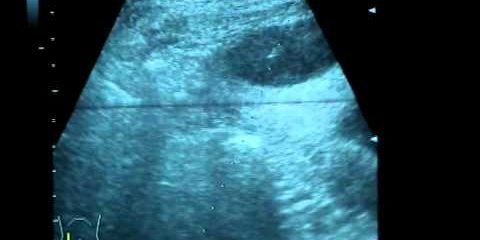

Техника выполнения чрескожной пункции подпеченочного абсцесса под УЗИ контролем